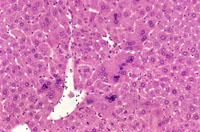

Adult mouse liver with scattered multinucleated hepatocytes

A mouse treated chronically with chlordane, showing enlarged hepatocytes with multiple nuclei.

Multinucleated hepatocytes in a B6C3F1 male mouse.